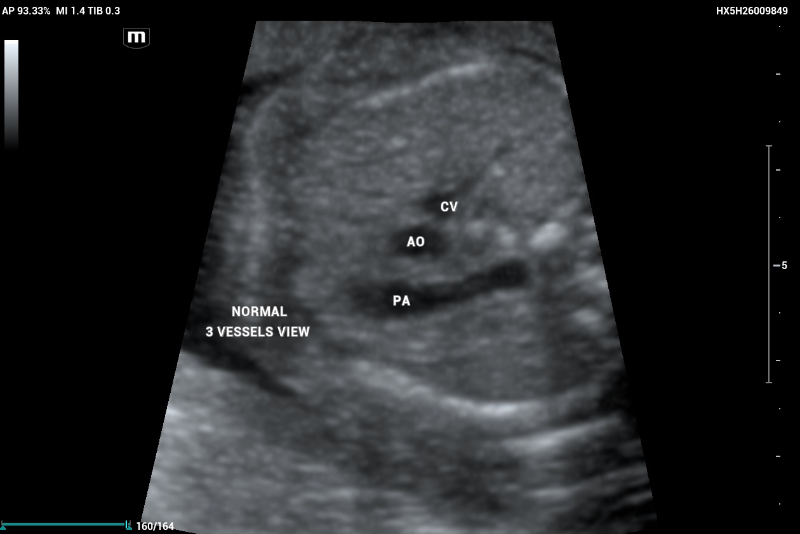

The three-vessel view (3VV) demonstrates the superior vena cava, aorta, and pulmonary artery, which should maintain a 1:1 size ratio (Figure 3).

An example of an axial thorax image showing a normal 3-vessel view demonstrates the presence of the cava vein (CV), aorta (AO), and pulmonary artery (PA) with similar size (relation 1:1)

Figure 3. An example of an axial thorax image showing a normal 3-vessel view demonstrates the presence of the cava vein (CV), aorta (AO), and pulmonary artery (PA) with similar size (relation 1:1).